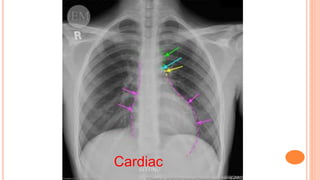

C Cardiac

On a PA image, the heart's width should be less than 50% of the chest width. On an AP image,

it should be between 50-60% of the chest width.

Cardiac